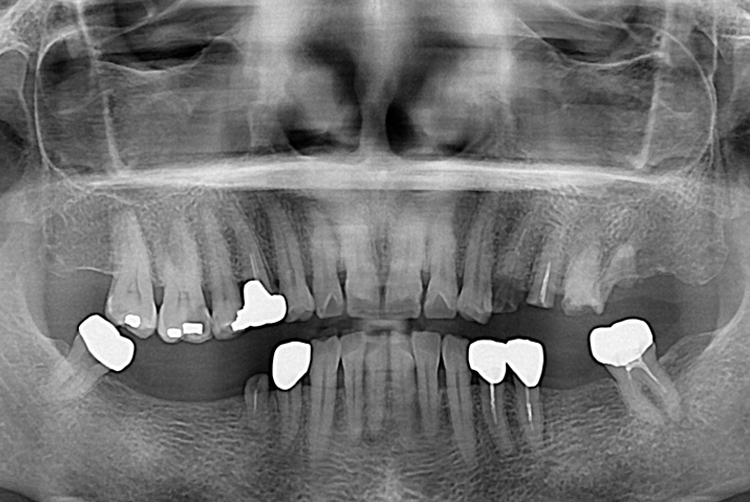

김명희_후.jpg

치료후 : 2018-09-21

세종치과는 많은 환자와 다양한 케이스를 바탕으로 항상 편안한 임플란트 수술을 제공하고자 노력하고,

오래동안 튼튼히 쓸 수 있는 임플란트 수술을 가장 큰 목표로 삼고 있습니다